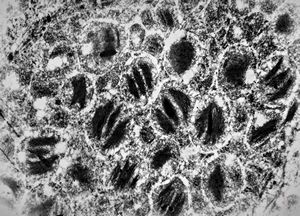

F,72y. | melanoblastoma oculi